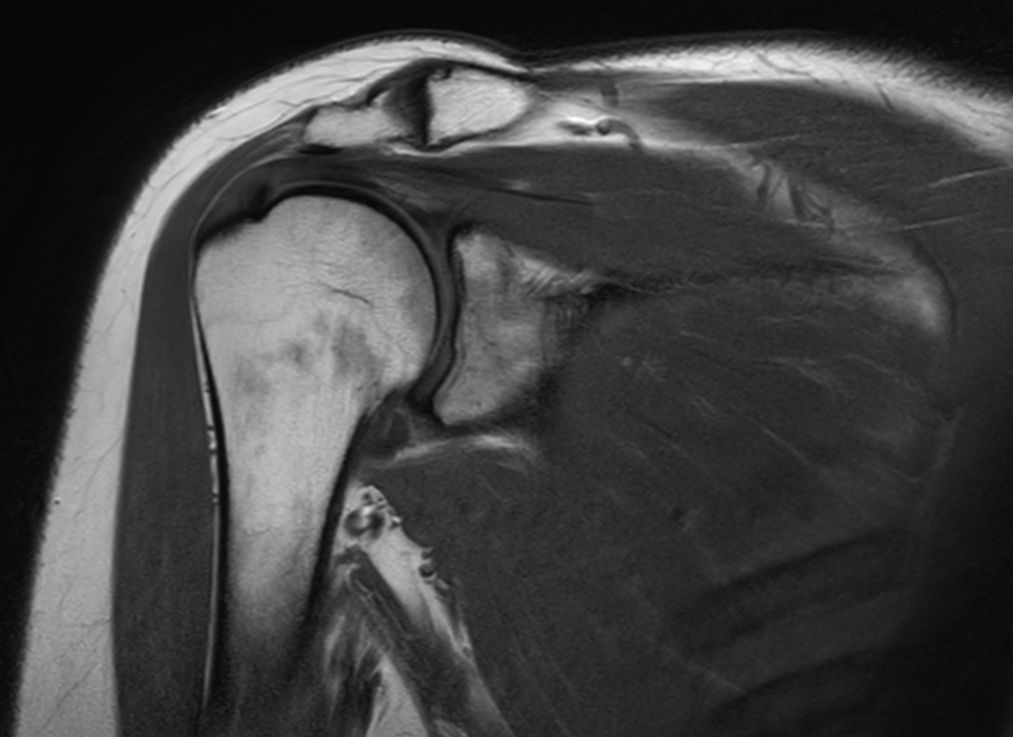

Coronal T1w TSE